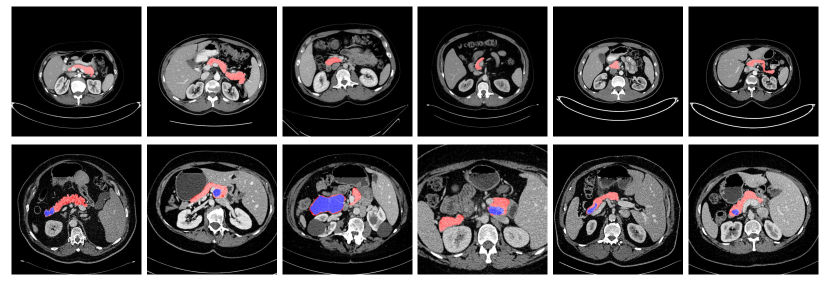

In this chapter, we focus on pancreas segmentation from CT scans, one of the most challenging organ segmentation problems zhou2017fixed roth2015deeporgan . As shown in Fig. 1, the main difficulties stem from three parts: 1) the small size of the pancreas in the whole abdominal CT volume; 2) the large variations in texture, location, shape and size of the pancreas; 3) the abnormalities, like pancreatic cysts, can alter the appearance of pancreases a lot.

As shown in Fig 4, we report the segmentation results by “ResDSN Coarse” and “ResDSN C2F” on the same slice for comparison. Note that yellow regions are the correctly predicted pancreas. For the NIH case , which is the min DSC case reported by both “ResDSN Coarse” and “ResDSN C2F”, the “ResDSN C2F” successfully predict more correct pancreas regions at the bottom, which is obviously missed by “ResDSN Coarse”. If the coarse segmentation is bad, e.g., case and , our 3D coarse-to-fine can significantly improve the segmentation results by as much as in DSC. However, if the coarse segmentation is already very good, e.g., case , our proposed method cannot improve too much. We conclude that our proposed “ResDSN C2F” shows its advancement over 2D methods by aggregating rich spatial information and is more powerful than other 3D methods on the challenging pancreas segmentation task.

We verified our proposed idea on the JHMI pathological cyst dataset zhou2017deep of abdominal CT scans as well. Different from the NIH pancreas dataset, which only contains healthy pancreas, this dataset includes pathological cysts where some can be or can become cancerous. The pancreatic cancer stage largely influences the morphology of the pancreas lasboo2010morphological that makes this dataset extremely challenging for considering the large variants.